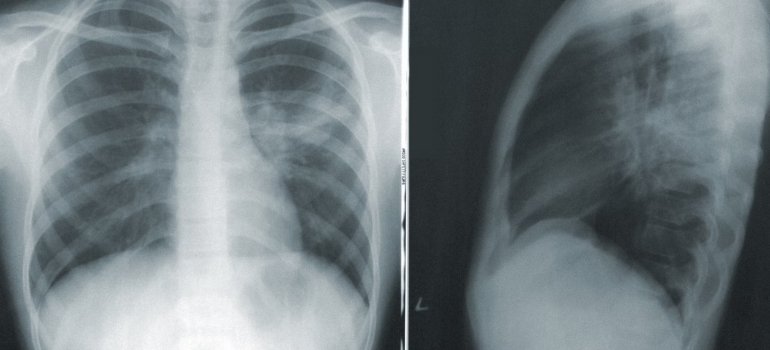

Рентген легких

Хотя рентген является частью диагностики эхинококкоза, необходимо провести дополнительные анализы.

Диагноз эхинококкоза устанавливается на основе анамнеза и физического обследования, рентгеновского снимка, ультразвукового исследования, компьютерной томографии и/или магнитно-резонансной томографии, а также с использованием определенных лабораторных анализов, включая биохимические и иммунологические исследования.

Помимо лабораторных анализов, инструментальная диагностика играет важную роль в локализации и характеризации гидатидных кист. Несмотря на широкое использование рентгена, он часто недостаточен для подробного исследования. Поэтому используются следующие методы: